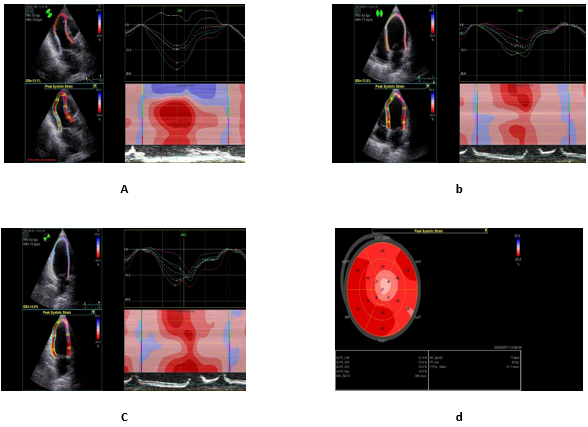

Speckle-Tracking Echocardiography: Peak longitudinal strain of the left ventricle was measured using speckle tracking echocardiography. Data analysis was performed offline using the original raw data sets on an Echo PAC software workstation (version BT11, 4D Auto LVQ; GE Vingmed Ultrasound AS) for semi-automated endocardial surface detection as the endocardial surface of the myocardial wall was manually traced by a point-to-click approach from which the software generates strain curves for each selected myocardial segment. Color-coded parametric images that provide a quick, visual impression of the timing and the extent of segmental myocardial deformation was generated (Figure 1).

Figure 1 Illustrations of the Steps involved in speckle tracking echocardiography. a,b,c; showing regional and global longitudinal strain obtained from the different apical views, d; a topographic representation of the regional and global longitudinal strain of all 17 analyzed segments (bull’s-eye configuration). Patient number 46.